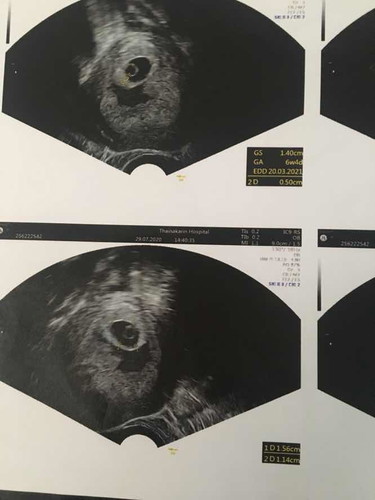

7 weeks ไม่เจอตัวอ่อน

ตอนนี้เราเสียใจมากๆ 7 สัปดาห์ ไปซาวด์ หมอบอกไม่พบตัวอ่อน เจอแต่ถุงตั้งครรภ์ กับถุงไข่แดง แถมยังมีเลือด อยู่ตรงโพรงมดลูก แต่เราไม่มีเลือดออกจากช่องคลอดเลย หมอบอกว่าเราเป็นแท้งคุกคามและแท้งค้าง มีใครเคยเป็นไหมคะ เรายังพอมีหวังไหม เสียใจมากก